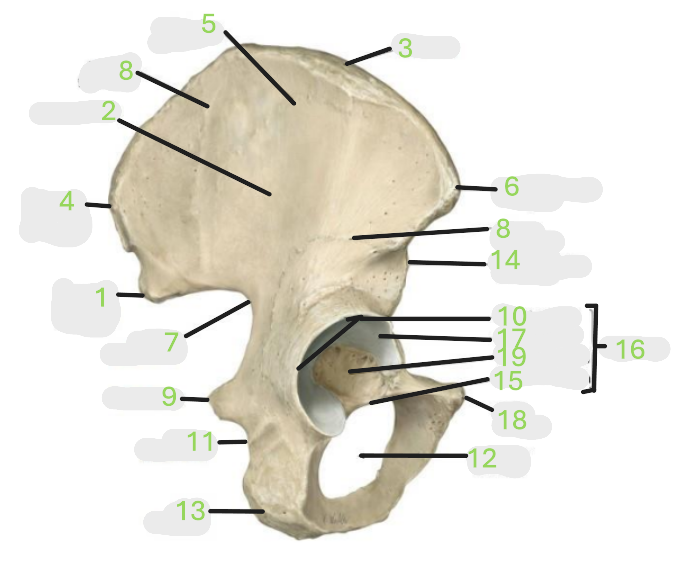

Where is the posterior inferior iliac spine

1

Where is the gluteal surface

2

Where is the iliac crest

3

Where is the posterior superior iliac spine

4

Where is the anterior gluteal line

5

Where is the anterior superior iliac spine

6

Where is the greater sciatic notch

7

Where is the inferior gluteal line

8

Where is the ischial spine

9

Where is the acetabular rim

10

Where is the lesser sciatic notch

11

Where is the obturator foramen

12

Where is the ischial tuberosity

13

Where is the anterior inferior iliac spine

14

Where is the acetabular notch

15

Where is the acetabulum

16

Where is the lunate surface

17

Where is the pubic tubercle

18

Where is the acetabular fossa

19